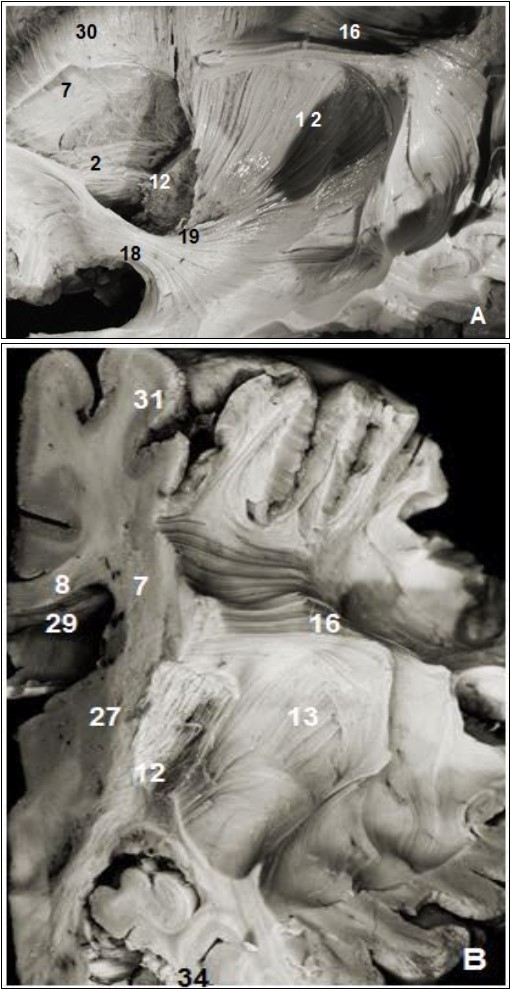

The internal capsule was exposed after the excision of the putamen and globus pallidus which were perfectly identifiable. The abscission of the outermost fibers of the internal capsule situated approximately 26 mm from the cerebral cortex and the head of the caudate nucleus exposed thalamic radiations (Figure 3).

Figure 4.(A) Lateral view of left cerebral hemisphere after dissection and (B) coronal view. 2. Anterior thalamic radiation, 7. Subependymal stratum, 8. Corpus callosum, 12. Internal capsule, 13. External capsule, 13. SLF, 15. Corona radiata, 16. Uncinate fasciculus, 19. Inferior frontal occipital fasciculus, 27. Putamen, 28. Globus pallidus, 29. lateral ventricle, 31. Parietal pole, 34. Temporal pole.

The inferior occipitofrontal fasciculus (Figure 2, Figure 4) closely attached to the previous fasciculus was composed of fiber bundles connecting the frontal lobe to the temporal, posterior parietal and occipital lobes. The IOFF is shaped somewhat like a flattened tape and is composed, as the uncinate fasciculus, of three parts: frontal, insular and parietal temporo-occipital segments.

The insular segment was fully exposed after the ablation of the uncinated bundle and courses medial to the external and extreme capsule and above the uncinate fasciculus. This segment was on average 2 mm thick and 8.8 mm wide.

The parietal temporo-occipital segment is about 20 mm wide stretching from the amygdala to the pulvinar and geniculate bodies at the height of the ventricular atrium.

The fanning frontal segment is located at the height of the frontal horn of the lateral ventricle. The frontal distribution of the inferior occipitofrontal fasciculus stretches to the whole of Broca's area. This frontal end was located 25 mm away from the cortex of the lower frontal gyrus. It is the second fasciculus connecting the frontal and the occipital lobes, and is thin at the frontal end.

The sub-ependymal stratum also known as the subcallosal stratum was made of a fiber-free layer of white matter. This layer of white matter was exposed after excision of the ependymal layer lining the ventricular system. It is located between the caudate nucleus and callosal radiations (Figure 1, Figure 2, Figure 4). Under the ependyma backward to the occipital horns, callosal fibers form together the tapetum and thalamic radiations. Our dissection failed to show a precise boundary between the tapetum and the sub-ependymal stratum. The substratum is a sub-ependymal structure located between the caudate nucleus, the corpus callosum radiations and the internal capsule. Globally, it is located below the ependyma and medial to the cingulum. It is not made of fibers connecting the frontal and the occipital lobes.